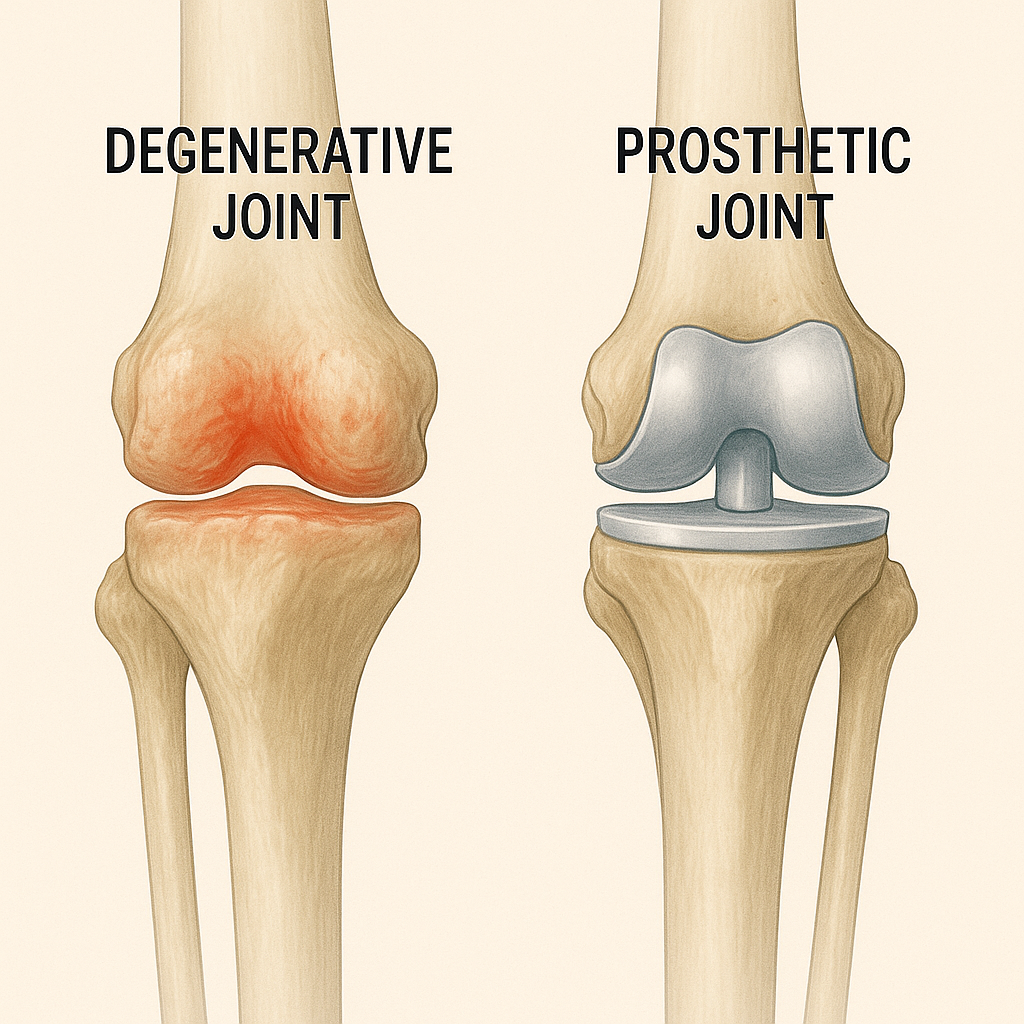

What Causes Joint Breakdown?

• Osteoarthritis – the most common culprit

• Post-traumatic arthritis – after fractures or sports injuries

• Avascular necrosis – blood flow loss to the joint

• Inflammatory arthritis – including rheumatoid disease

Cartilage wears down, inflammation builds, and motion becomes painful.

When Should You Consider Joint Replacement?

It’s not about X-rays — it’s about quality of life. You might be ready if:

• Pain keeps you from walking, working, or sleeping

• Conservative care (PT, injections) isn’t working

• You’ve had enough of the “just wait and see” approach

• Imaging shows bone-on-bone wear

You don’t need to wait until it’s unbearable.